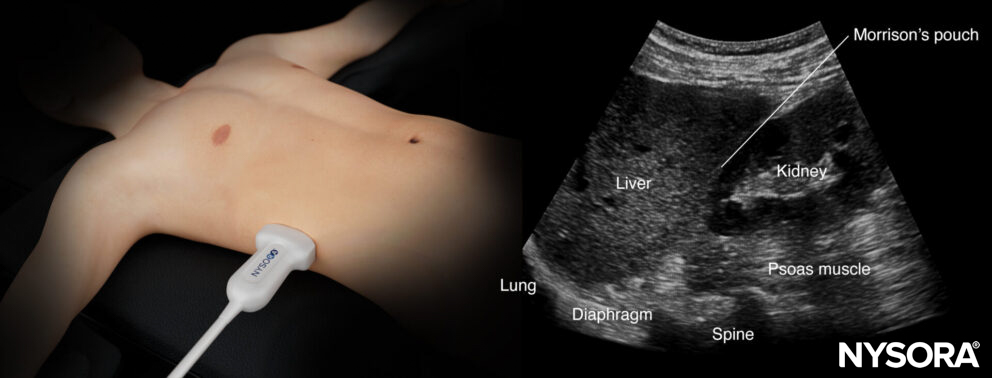

Right upper quadrant (RUQ)

Detects free fluid in the right thorax and abdomen.

- Position the transducer between the mid- and posterior axillary lines at the level of the xiphoid process, with the orientation marker facing the patient’s head.

- Scan caudally until you visualize the liver and the kidney; fluid usually collects between the liver and the kidney, i.e., Morrison’s pouch.

Structures of interest: lung, diaphragm, liver, kidney, Morrison’s pouch (virtual space between liver and kidney)

Normal sonoanatomy:

Ultrasound anatomy of the right upper quadrant and relevant anatomical structures.

Reverse ultrasound anatomy of the right upper quadrant and relevant anatomical structures.